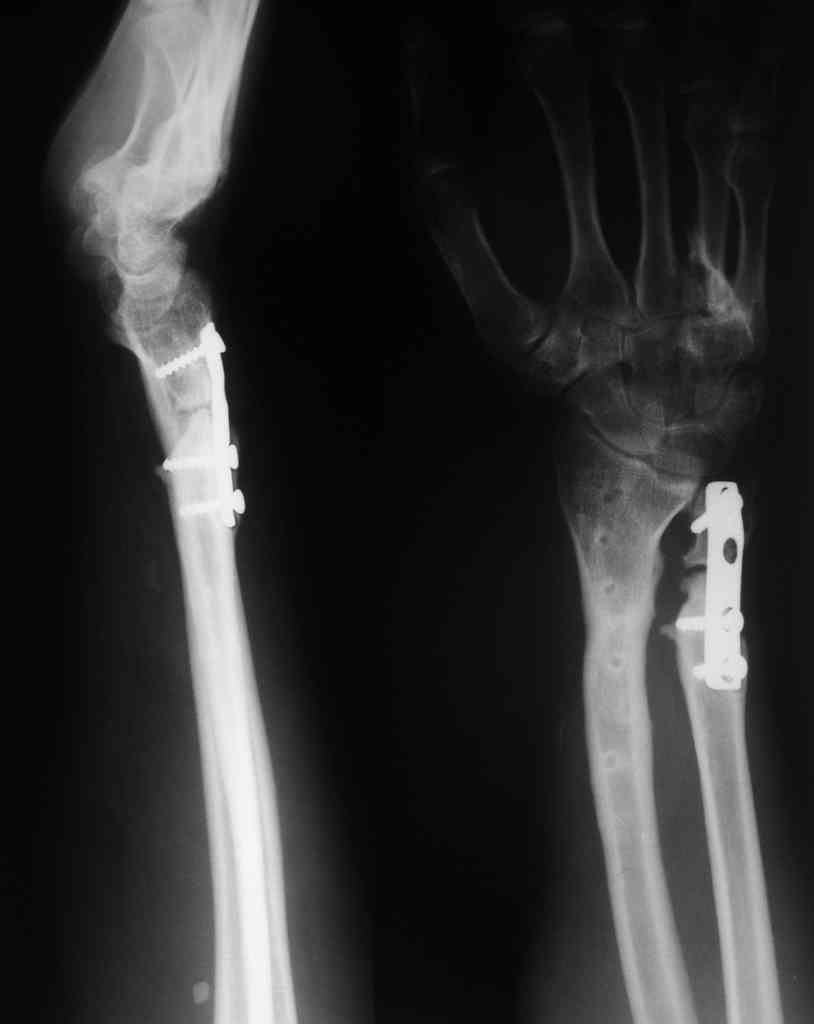

Судя по показанным Рг граммам, очевиден посттравм. артроз лучезапястного сустава, проблема дистального радиоульнарного сочленения(TFCC).

Угол наклона лучевой фасетки в норме в пределах 10-15 градусов, на представленном боковом снимке -может быть чуть больше 15градусов. Выполнив

разгибательную остеотомию луча, ты поставишь фасетку в нейтральное положение и таким образом увеличится угол разгибания , но уменьшится сгибание. По сути, амплитуда движений останется такой же.

Первым этапом я бы убрал пластину с последующей ограниченной резекцией головки локтевой кости(hemiresection and interposition arthroplasty Bowers technique). провести курс реабилитации. если уровень мобильности сустава не

будет устраивать больного, можно рассмотреть проксимальную карпальную резекцию в качестве последующего этапа.

Не думаю, что несращение локтевой кости является критичным в данных условиях, когда необходимо добиваться её консолидации - в условиях

контрактуры радио-ульнарного и лучезапястного сустава . Описана техника создания дистального радиоульнарного артродеза с преднамеренным созданием псевдоартроза локтевой кости( ограниченная резекция её на уровне

дистального метадиафиза - Сауве-Капанджи). Посмотри описание в Кэмбел 4 том, 10 -ое издание , стр. 3577.